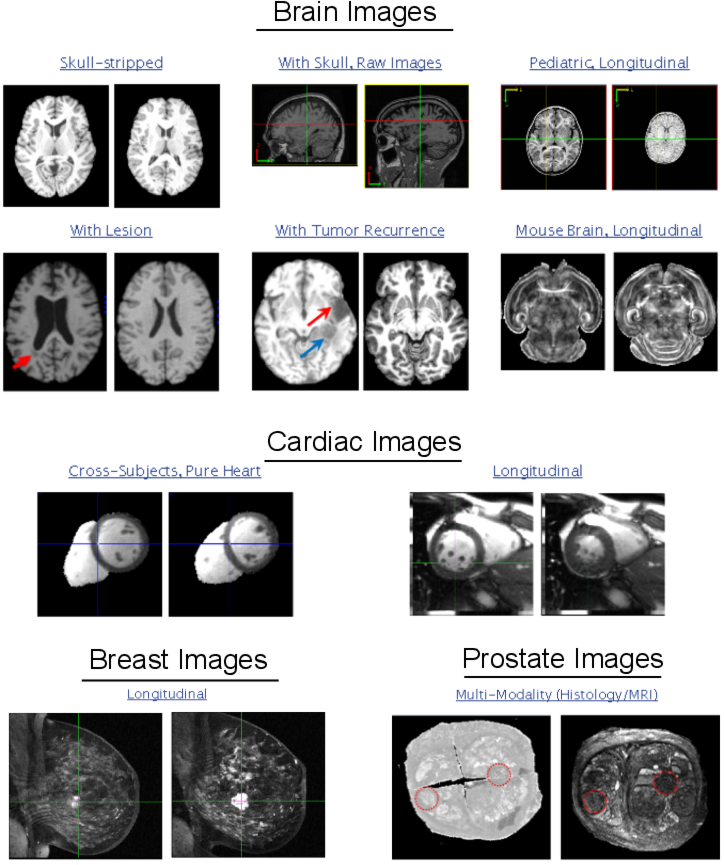

-- Cross-subject registration of the same organ (can be brain, breast, cardiac, etc);

-- Mono- and Multi-modality registration (MRI, CT, histology);

-- Longitudinal registration (pediatric brain growth, cancer development, mouse brain development, etc);

-- Registration under missing correspondences (e.g., vascular lesions, tumors, histological cuts).

Project Samples